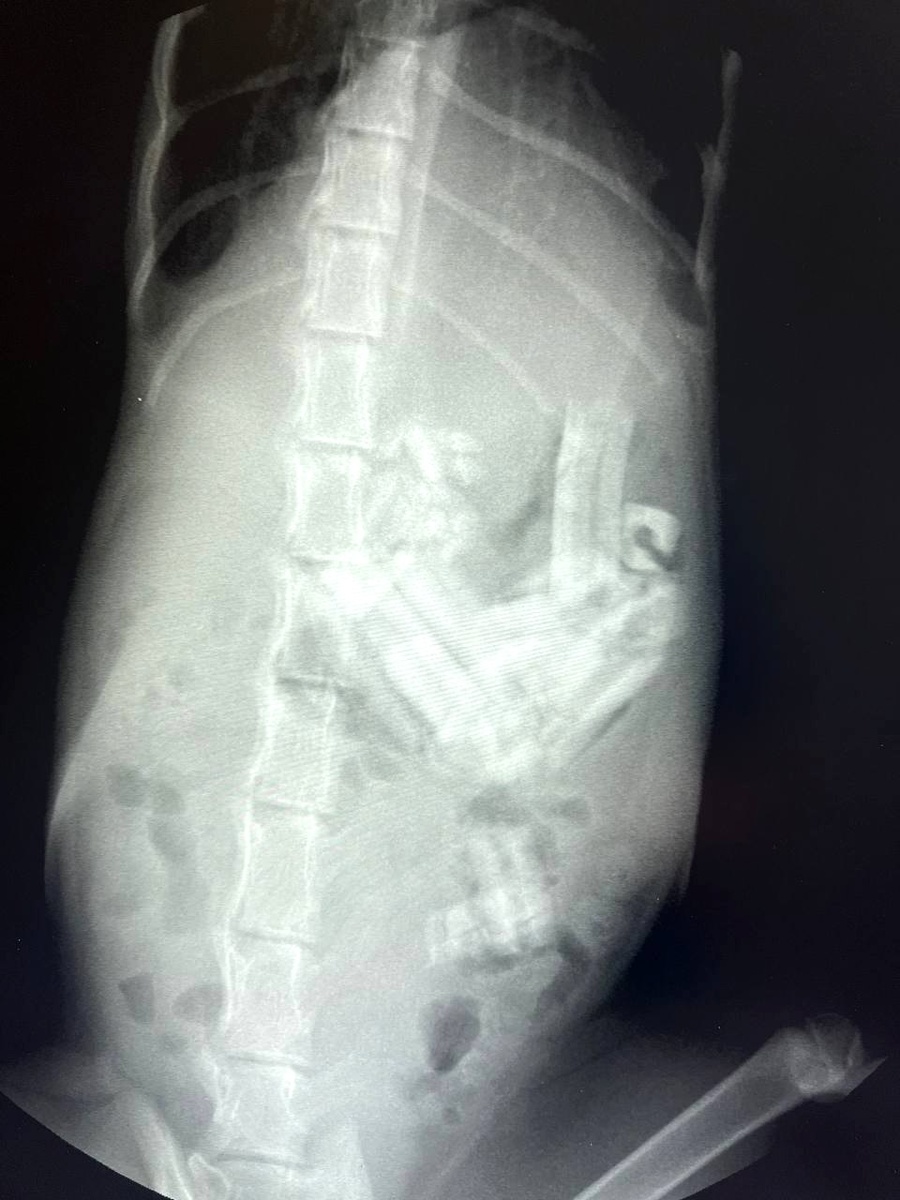

После обследования стало ясно: в желудке находится порядка 20 кусков резинки. Ещё два куска обнаружились в 12-перстной кишке, а также в тонком кишечнике.

Рентген Джесси.  Фото. Telegram-канал «Моя Ветклиника»

Все двадцать кусков удалось извлечь в ходе ЭГДС. Сделал это гастроэнтеролог и эндоскопист Ярослав Никифоров во время обследования верхней части ЖКТ. Размер инородных тел — 1-2 см.